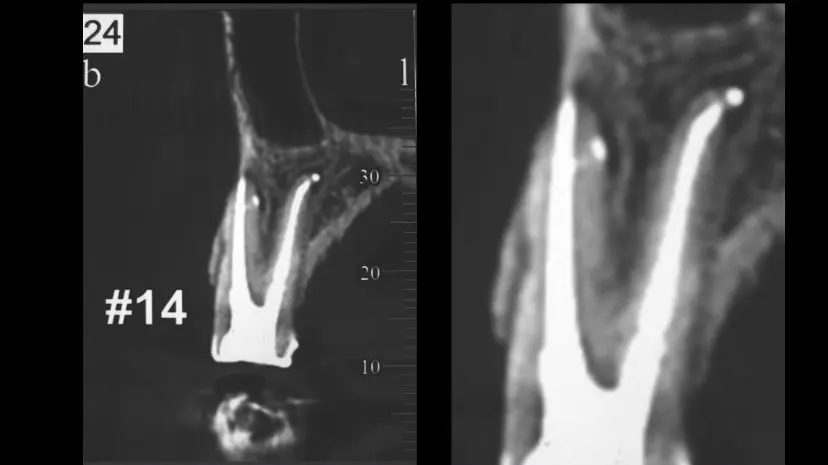

這種治療結果不是天天都看得到,很多時候得要靠運氣以及醫師的經驗。乍看兩張根管治療重新治療前後的X光片,一般患者大概看不出什麼差別,即使是牙醫師有時候也得改變拍攝角度去嘗試自己辛苦努力的成果。

這位患者因為需要電腦斷層影像來做其他位置的診斷,剛好有機會得以看見一個教案等級的根管充填,尤其是這個刁鑽的側枝小開口,傳統的X光片很難如此清楚的呈現。低調的張醫師呈現出他的治療品質,從來德十八年前開始,就一直提供高水準的根管治療。